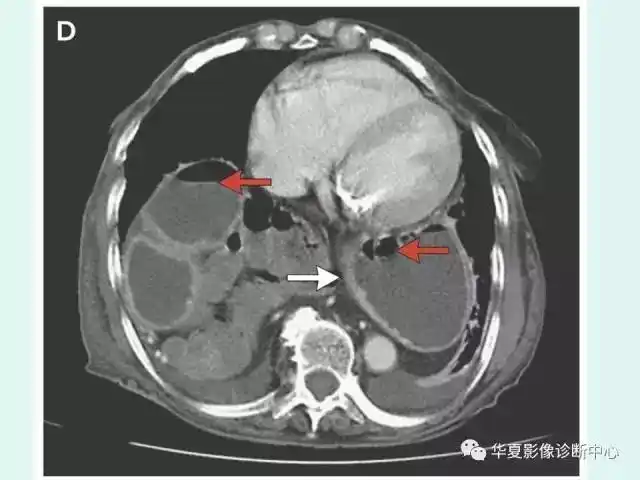

转贴食管裂孔疝

食管裂孔疝

食道裂孔疝1例影像表现

经典影像之食管裂孔疝 - 好大夫在线